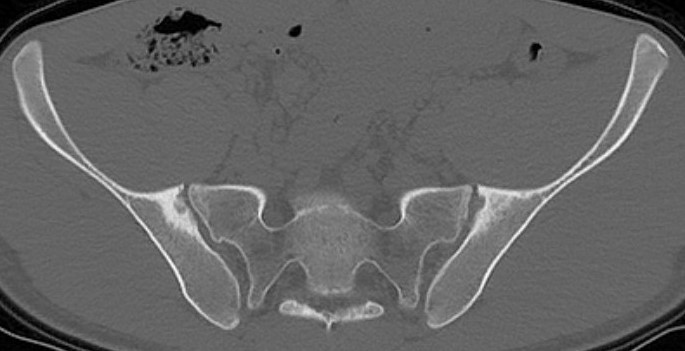

Sacro-iliac joint

- erosion / sclerosis / finally ankylosis